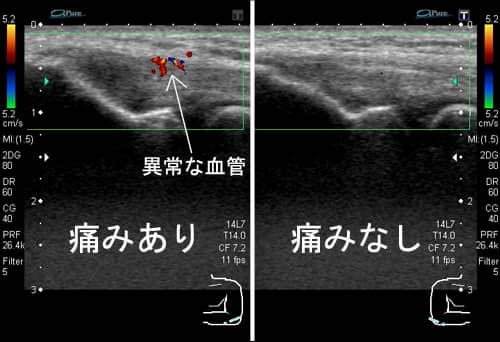

「痛み」はエコーで見える?見えない?

[記事提供:オクノクリニック | モヤモヤ血管による慢性痛治療(https://okuno-y-clinic.com)]…